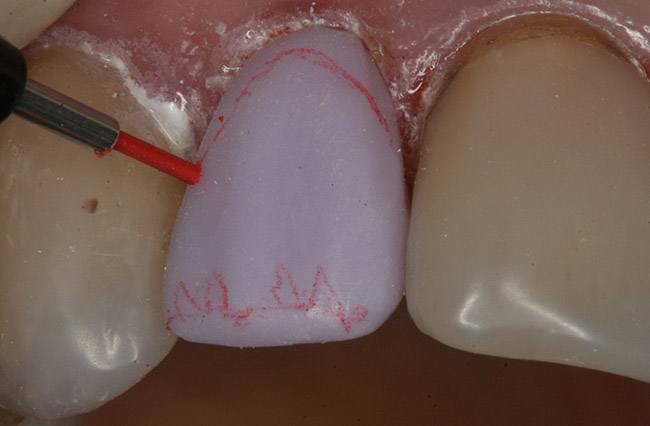

The next step was to draw a map of the staining scheme with a red wax margin liner pencil on the facial surface of the crown (Figure 14). The use of the red wax pencil allows the clinician to visualize the color map of the matching tooth and draw areas to receive the appropriate stain (similar to a “paint by numbers” exercise). Instead of using the glaze liquid that is supplied by the manufacturer, distilled water is used to mix the stains. The water evaporates much faster than the glaze liquid and prevents, along with the red wax pencil line, the stains running together. Using a fine brush, the stains were placed in the appropriate areas. This “stain within the lines” technique simplifies the staining process (Figure 15). The temperature of the crystallization cycle burns off the red wax without leaving any residue. The crown was then carefully removed from the patient’s mouth.

Figure 14  A map of the staining scheme with a red wax margin liner pencil on the facial surface of the crown was drawn.

Figure 14